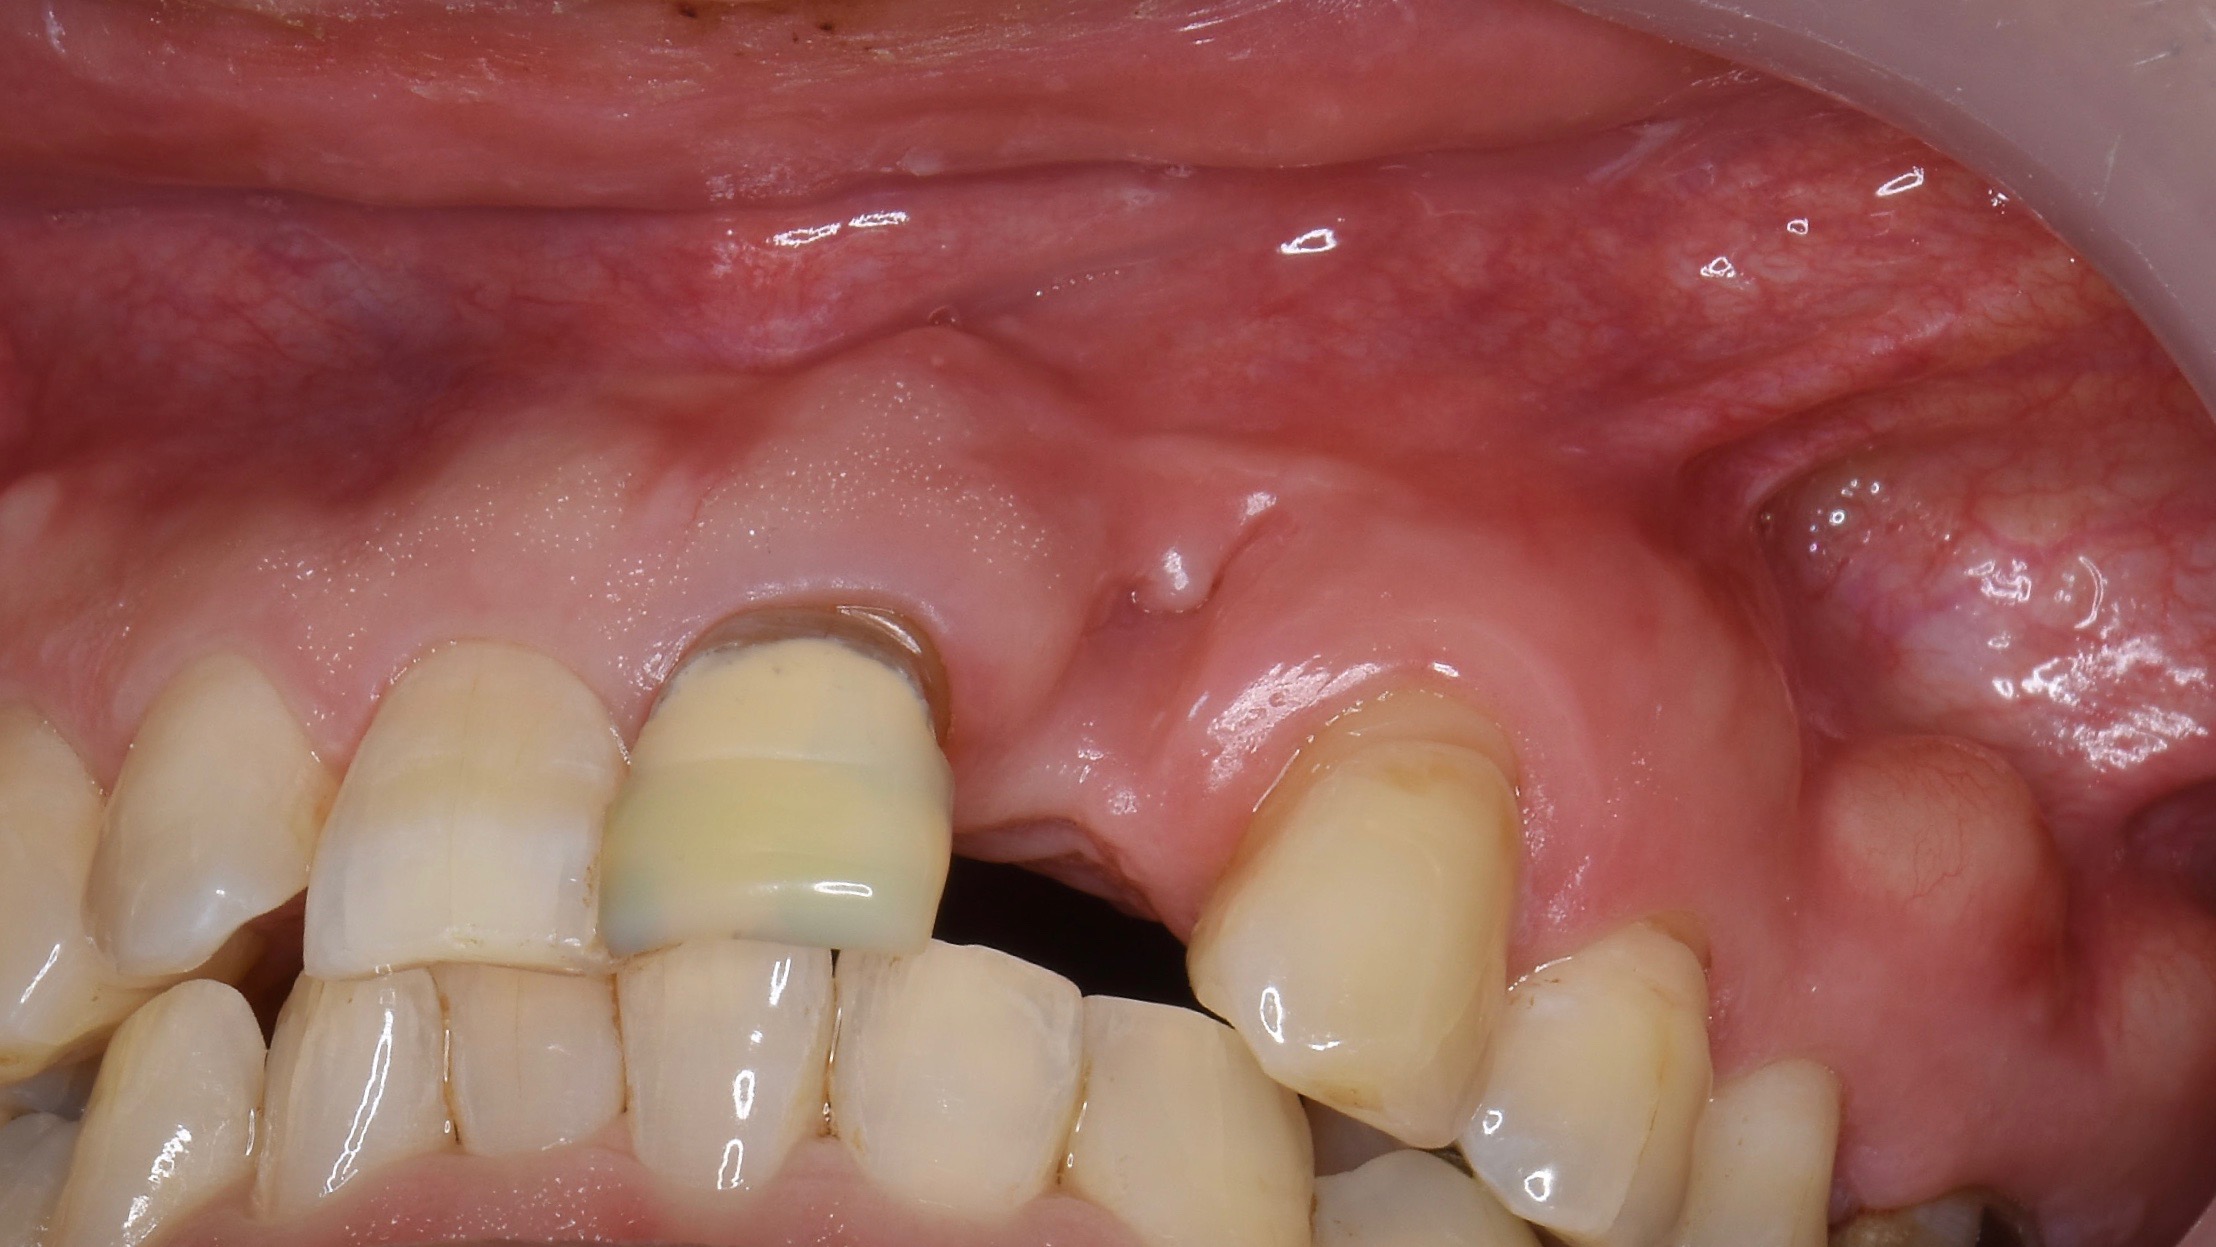

左下のインプラント予定部。

切開して開けてみると、2ヶ月前の抜歯跡が見受けられた。しかし

当院では骨の再生治療をインプラント移植時に同時進行で施しているので、全く問題はありません。

骨のない所に人工骨のβ–TCPを添加して、本物の骨に置換するのを待ちます。

左下の施術終了。